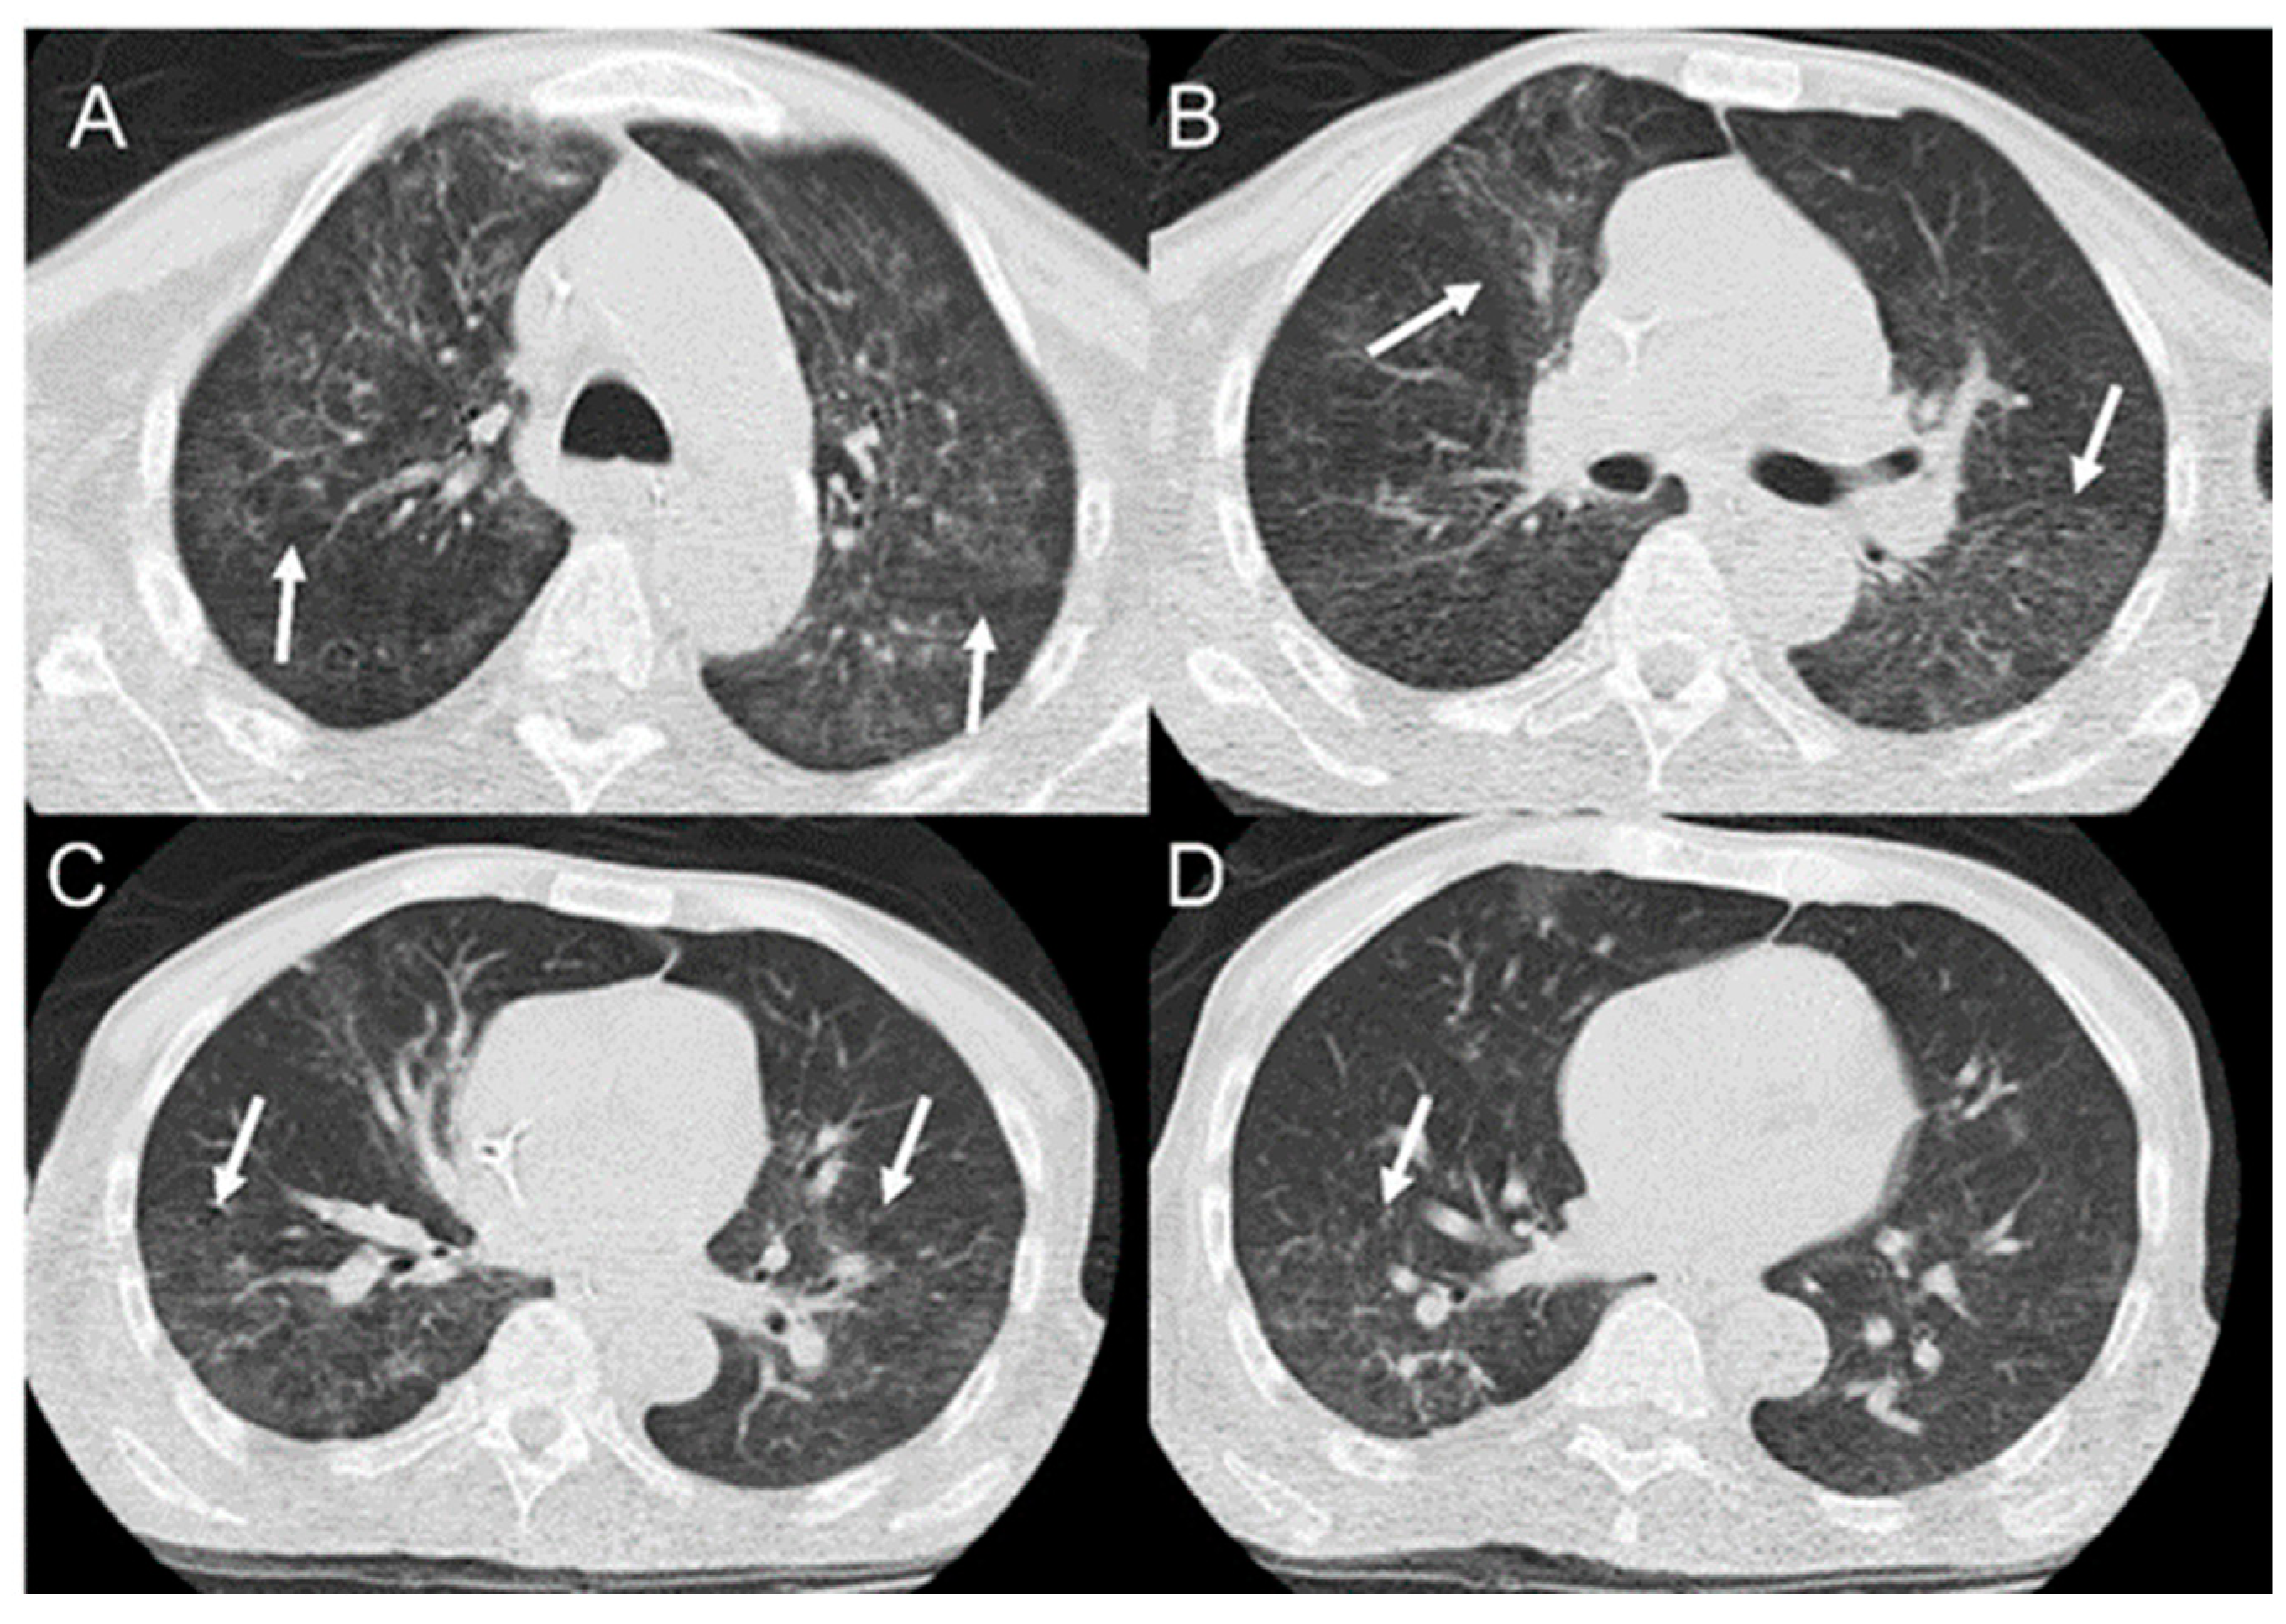

- Rosa Junior, M.; Baldon, I.V.; Amorim, A.F.C.; Fonseca, A.P.A.; Volpato, R.; Lourenco, R.B.; Baptista, R.M.; de Mello, R.A.F.; Pecanha, P.; Falqueto, A. Imaging paracoccidioidomycosis: A pictorial review from head to toe. Eur. J. Radiol. 2018, 103, 147–162. [Google Scholar] [CrossRef]

- Queiroz-Telles, F.; Escuissato, D.L. Pulmonary paracoccidioidomycosis. Semin. Respir. Crit. Care Med. 2011, 32, 764–774. [Google Scholar] [CrossRef]

- Queiroz-Telles, F.V.; Pecanha Pietrobom, P.M.; Rosa Junior, M.; Baptista, R.M.; Pecanha, P.M. New Insights on Pulmonary Paracoccidioidomycosis. Semin. Respir. Crit. Care Med. 2020, 41, 53–68. [Google Scholar] [CrossRef]